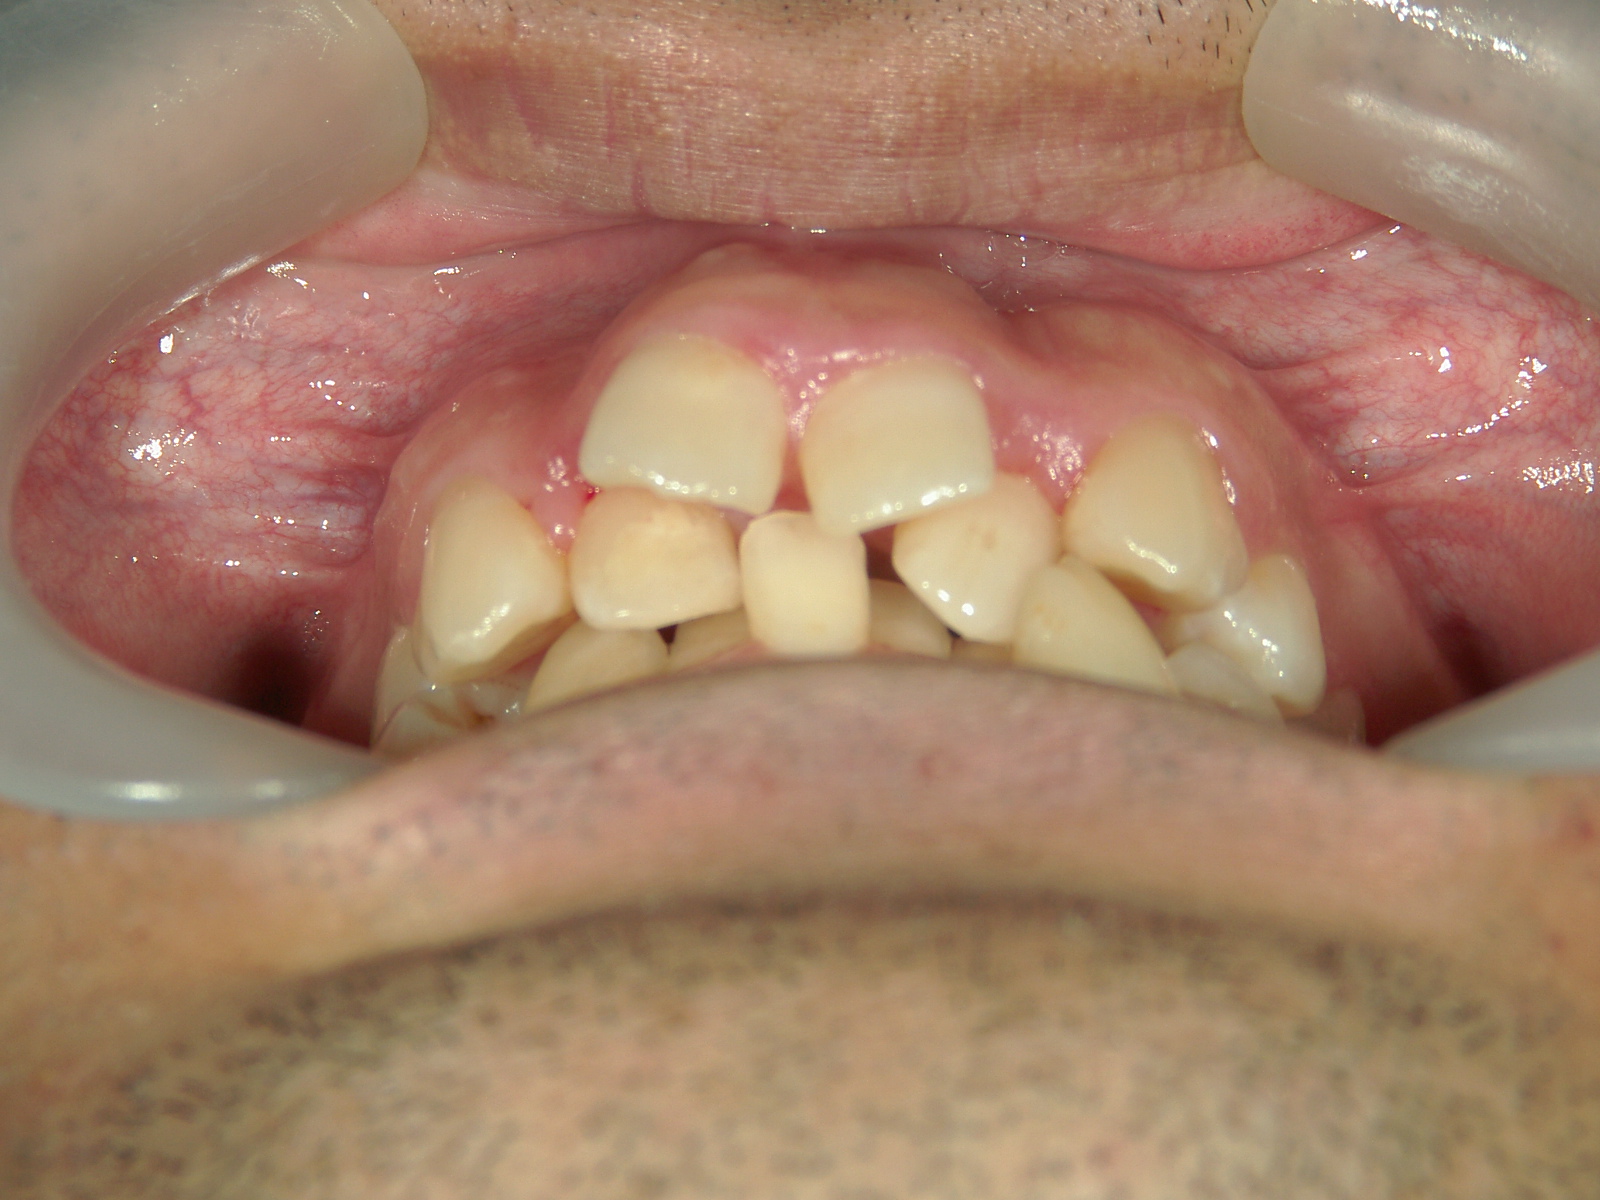

全顎ワイヤー矯正 症例(79)

主訴: 前歯が噛み合わない。歯並びが気になる。

カテゴリー : ガタガタ(叢生) , 噛み合わせが深い(過蓋咬合)